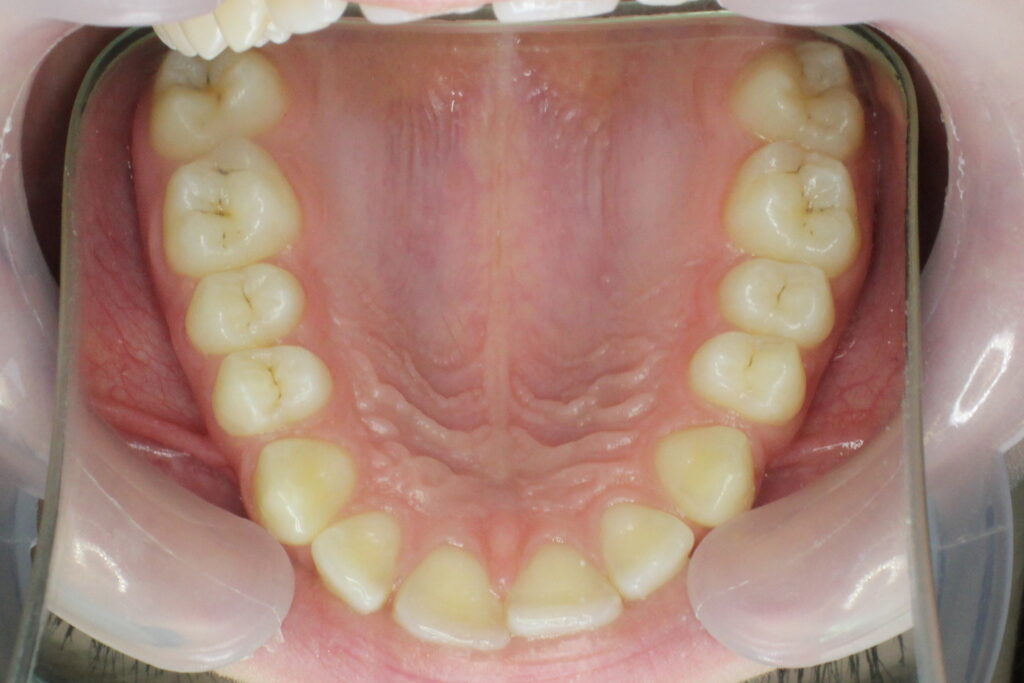

Ситуация до лечения

Диагноз: дистальный прикус, сужение, удлинение верхнего зубного ряда, скученность фронтальной группы зубов на нижней челюсти. Лечение проводилось самолигирующей брекет-системой Damon Q, срок лечения составил 2 года и 2 месяца.

Ситуация до лечения брекетами